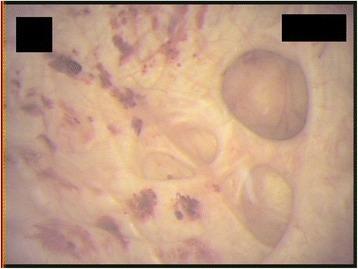

Emphysematous cystitis is a very rare complicated urinary tract infection characterized by air in the bladder wall.

We report two clinical cases of emphysematous cystitis of an 83-year-old Caucasian woman with diabetes mellitus and a 78-year-old Caucasian man with no past medical history. They presented with severe confusion and abdominal distension. Emphysematous cystitis was diagnosed in time with a thorough physical examination, urine analysis and computed tomography. The patients were successfully treated with antibiotic therapy and bladder drainage.